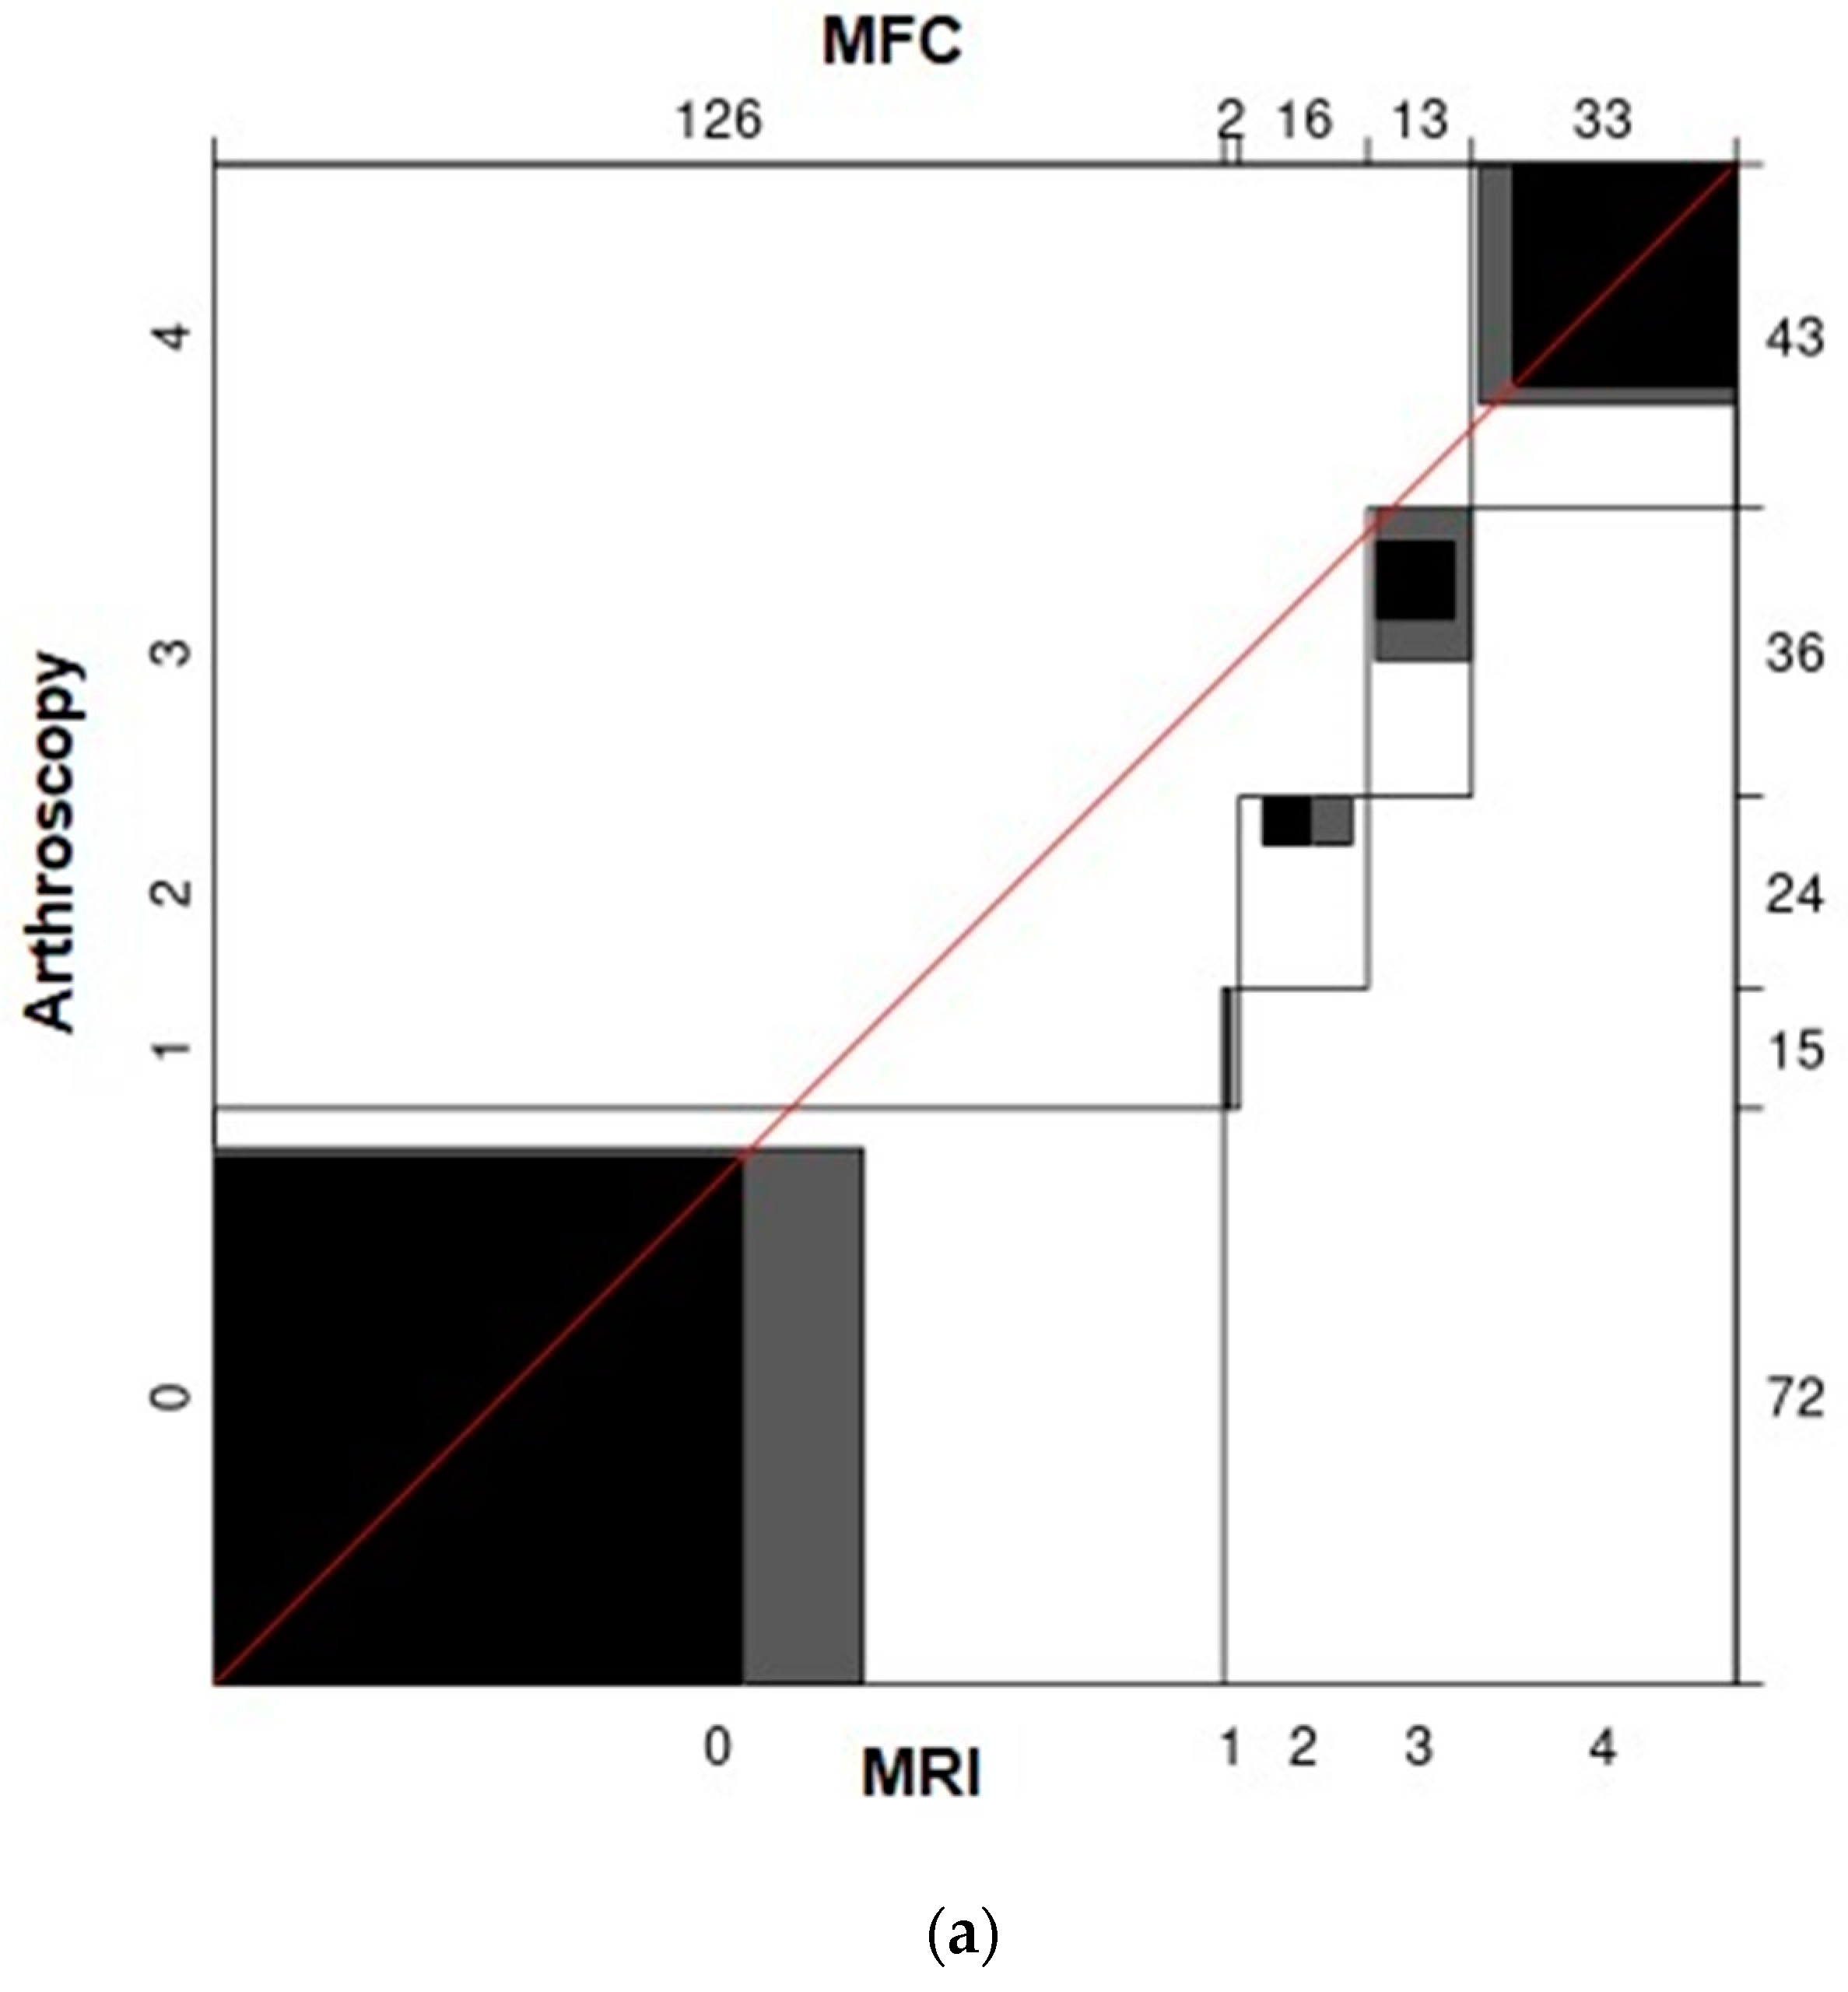

3. Results

| Location | Cartilage Status According to ICRS | Cartilage Lesions in Total | ||||

|---|---|---|---|---|---|---|

| 0 | 1 | 2 | 3 | 4 | ||

| MFC | 72 | 15 | 24 | 36 | 43 | 118 |

| LFC | 113 | 29 | 25 | 19 | 4 | 77 |

| MTC | 99 | 23 | 32 | 19 | 17 | 91 |

| LTC | 113 | 32 | 28 | 11 | 6 | 77 |

| PFJ | 100 | 20 | 24 | 24 | 22 | 90 |

| Total | 497 | 119 | 133 | 109 | 92 | 453 |

| Value | ASE | z | ||

|---|---|---|---|---|

| MFC | Unweighted | 0.39 | 0.046 | 8.387 |

| Weighted | 0.57 | 0.054 | 10.684 | |

| LFC | Unweighted | 0.13 | 0.042 | 3.015 |

| Weighted | 0.36 | 0.077 | 4.739 | |

| MTC | Unweighted | 0.29 | 0.047 | 6.094 |

| Weighted | 0.56 | 0.064 | 8.777 | |

| LTC | Unweighted | 0.10 | 0.041 | 2.473 |

| Weighted | 0.35 | 0.092 | 3.819 | |

| PFJ | Unweighted | 0.38 | 0.049 | 7.626 |

| Weighted | 0.50 | 0.069 | 7.335 |